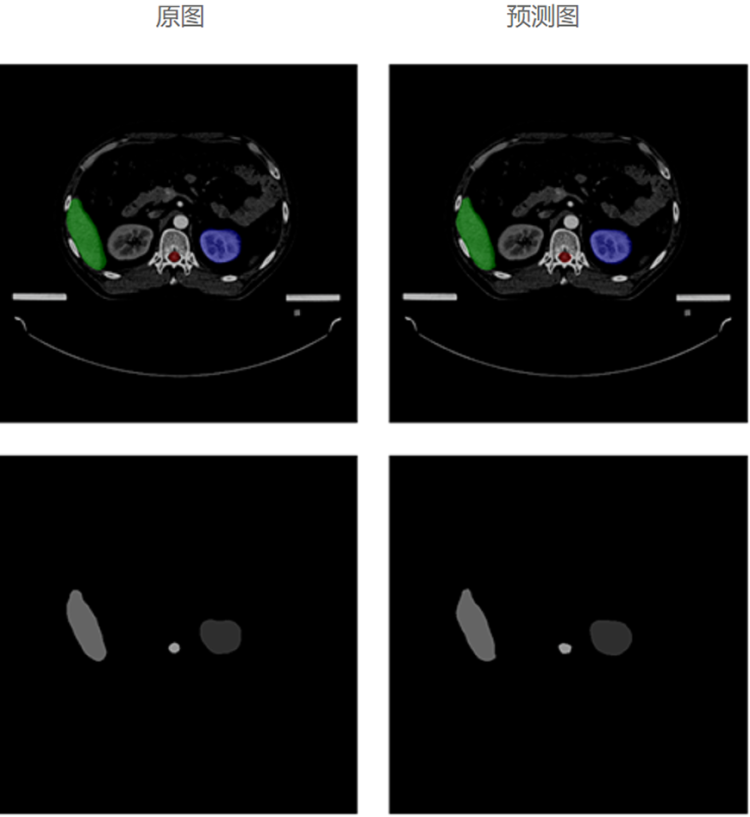

自动勾画效果

基于海量优选的专家勾画结构数据,利用深度学习人工智能技术,大力发展放疗智能勾画,自动勾画出精准且符合病人个性化特性的结果,帮助医生更加快速、准确地勾画肿瘤靶区和危及器官,从而推动放疗乃至肿瘤医疗的精准化、智能化发展,大大提高放疗勾画的工作效率。

模型经过对海量勾画结构数据的学习,以及改进优化,再进过大量样本数据训练及验证,自动勾画结果的平均准确度已达92%以上。